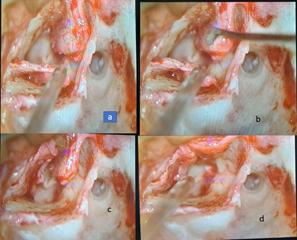

A fascia graft was then positioned medial to the anterior tympanic remnant and over the malleus handle before being draped onto the posterior canal wall (Figure 2).

Figure 2 (a-c) Insertion of temporalis fascia along with elevated superior and inferior tympanomeatal flaps. (d-e) both flaps repositioned over the meatal wall, showing the defect covered adequately with graft.

Finally, the swinging door flaps were rotated onto the fascia graft to ensure its secure positioning and placement (Figure 3).

Figure 3 (a,b,d) Fascia graft tucked under TM flap. (c,e) Checking of graft tucking under inferior tympanomeatal flap. (f) Final stage after checking all quadrants of graft placement with visible single 3 o’clock incision in the left ear.